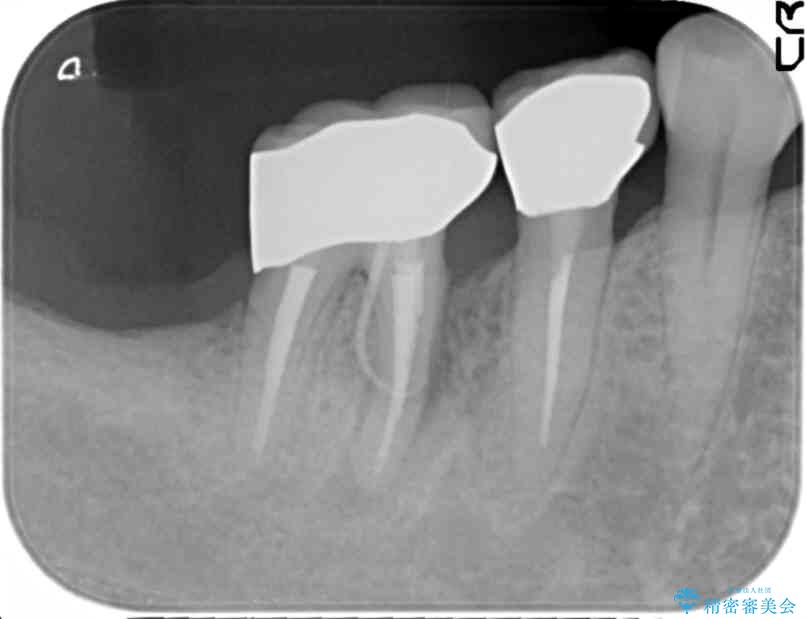

治療前

奥歯から膿のにおいがする インプラントによる機能回復 治療前画像 奥歯から膿のにおいがする インプラントによる機能回復 治療前画像 奥歯から膿のにおいがする インプラントによる機能回復 治療前画像 奥歯から膿のにおいがする インプラントによる機能回復 治療前画像 奥歯から膿のにおいがする インプラントによる機能回復 治療前画像 奥歯から膿のにおいがする インプラントによる機能回復 治療前画像

精査した結果、奥歯の根は破折しており抜歯を避けられない状況でした。